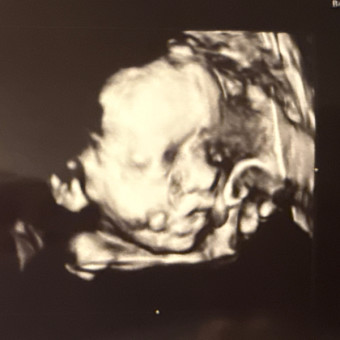

Baby T 🩵

Carly & George Tschappat

July 1, 2026